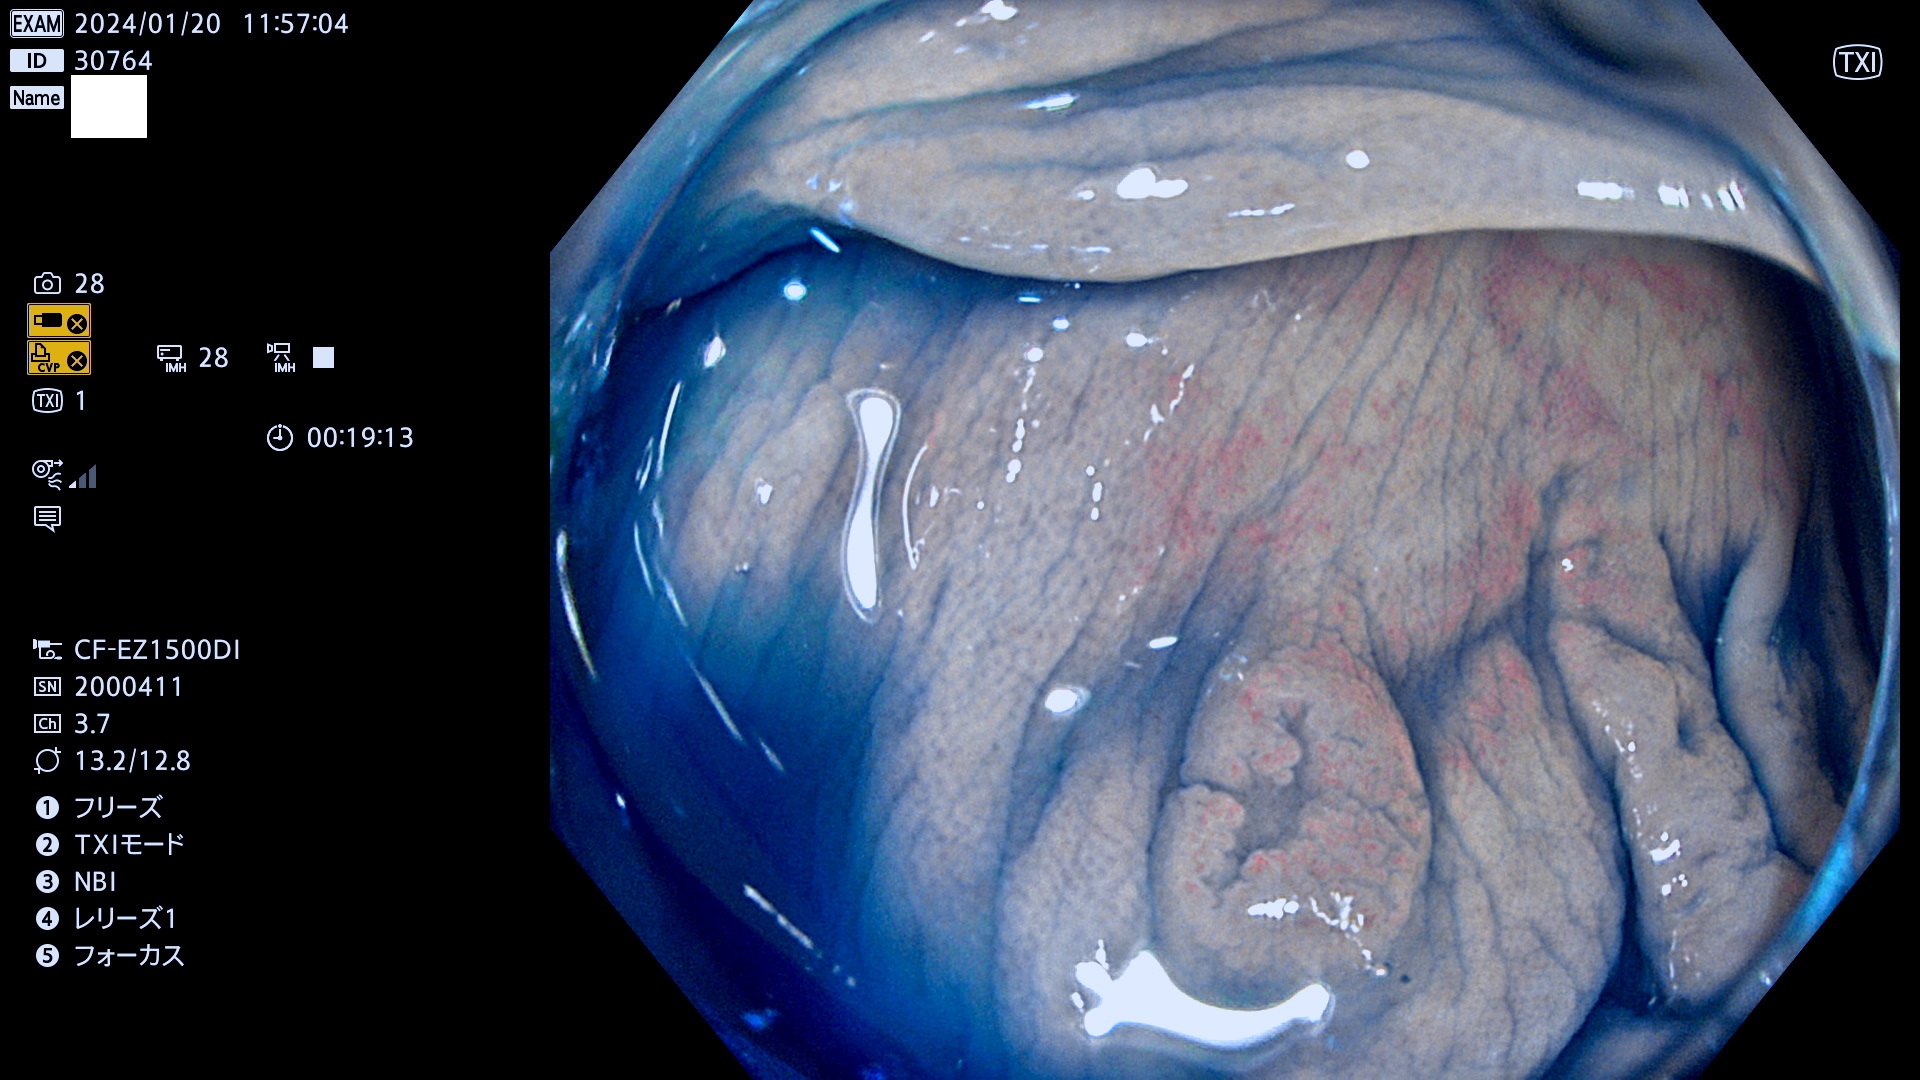

表面型腺腫(Flat Adenoma)の中で、完全に平坦な物をUb、陥凹している物をUcと呼びます。平坦隆起型(Ua)よりも、発見が難しく危険な病変です。

毎週の検査(木・金・土・日)に発見されたUb、Uc型・腺腫を、その週の日曜の夜にUPし1週間、提示します。

抽出の対象期間 2024年1月18日(木)〜1月22(月)の5日間(50件の検査)7件